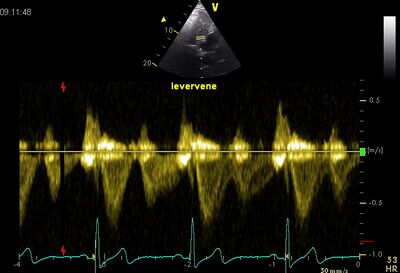

Flow pattern

Because in most cases VCI is perpendicular to the beam in the ultrasound image running, the flow pattern of the hepatic vein viewed . This is the same as VCI, only the hepatic vein is parallel to the sound beam .

Normal hepatic vein flow Systolic flow reversal of the hepatic vein in severe TI 1